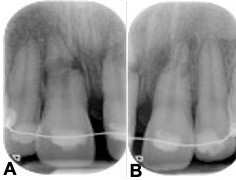

The radiological aspect of no healing is shown in Figure 1. No healing occurs if the pulp of the coronal fragment becomes necrotic and infected, with interposition of granulation tissue that extends into the adjacent bone and evidence of radiolucency extending laterally. Figure 1 also shows external inflammatory resorption in the apical third of the root and signs of bone periapical radiolucency.

Cone beam computed tomography (CBCT) may often be required as a follow-up to assess the involvement of surrounding tissues, the amount of external and internal root resorption on the involved teeth, the anatomy of the root fracture of the apical third, and displacement of the coronal segment. Figure 2 and Figure 3 illustrate CBCT parasagittal images that confirm the results of the intraoral radiographs. The diastasis between the coronal and apical fragments of #11 appear to be more evident on the fracture line and the presence of a “new apical foramen” is highlighted. In addition, areas of external inflammatory resorption on the apical fragment are evident and the fracture line appears jagged. The images relating to #21 appear suggestive for external inflammatory resorption, particularly on the vestibular side, which is the site of concomitant bone inflammation in the parasagittal image #48. Internal pulp resorption can also be observed at the apical third of the root.